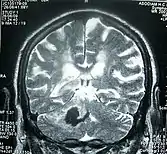

Perinatal stroke can be diagnosed with medical imaging techniques that present the brain's image. The usage of diffusion-weighted imaging with magnetic resonance imaging is effective for early diagnosis of perinatal stroke.[18] Computerized tomography (CT) is also a commonly used diagnostic technique for this disease.[35] These medical imaging techniques can show bleeding or blockage in the brain and detect damage caused by ischemic stroke or hemorrhages to the brain tissues.[36] Magnetic resonance imaging is clinically preferred to computerized tomography as it can highlight the brain's blood flow.[35] In addition, perinatal stroke is challenging to classify on computerized tomography as the neonatal brain has higher water content.[7][36] However, in certain situations, such as the inability to transport unstable infants with severe respiratory or cardiac disorders from the intensive care unit, cranial ultrasound is used as an alternative to magnetic resonance imaging.[7] Cranial ultrasound can identify intracranial hemorrhage, intraventricular hemorrhage, large cerebral sinus venous thrombosis along with the brain's blood flow.[7]